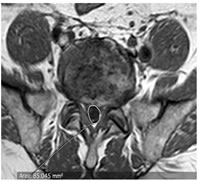

CASE 2

T1 AND T2 W AXIAL IMAGES SHOWING DIFFUSE DISC BULGE WITH SEVERE BILATERAL FACETAL ARTHROPATHY AND LIGAMENTA FLAVA THICKENING AT L5-S1 LEVEL CAUSING MODERATE THECAL SAC STENOSIS, NARROWING OF LATERAL RECESS WITH COMPRESSION OVER BILATERAL TRAVERSING NERVE ROOTS. AN INTRASPINAL SYNOVIAL CYST IS ALSO SEEN ARISING FROM FACET JOINT ON THE RIGHT.

AXIAL T1 AND T2 W IMAGES SHOWING HYPOINTENSE SIGNAL ON PEDICLE OF S1 VERTEBRA ON LEFT SIDE SUGGESTIVE OF SCLEROTIC LESION POSSIBLY OSTEOMA